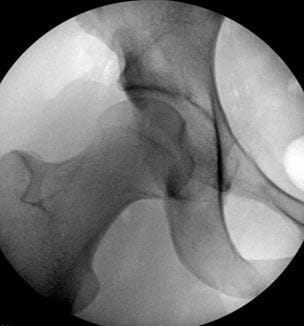

Novel Dual Hip Preservation Technique Grows in International Prominence

Innovations in Orthopaedics | Summer 2024

A Joint Effort

New, collaborative approach to treating young adult hip dysplasia combines two procedures in one surgery - UH Department of Orthopaedics | Winter 2018